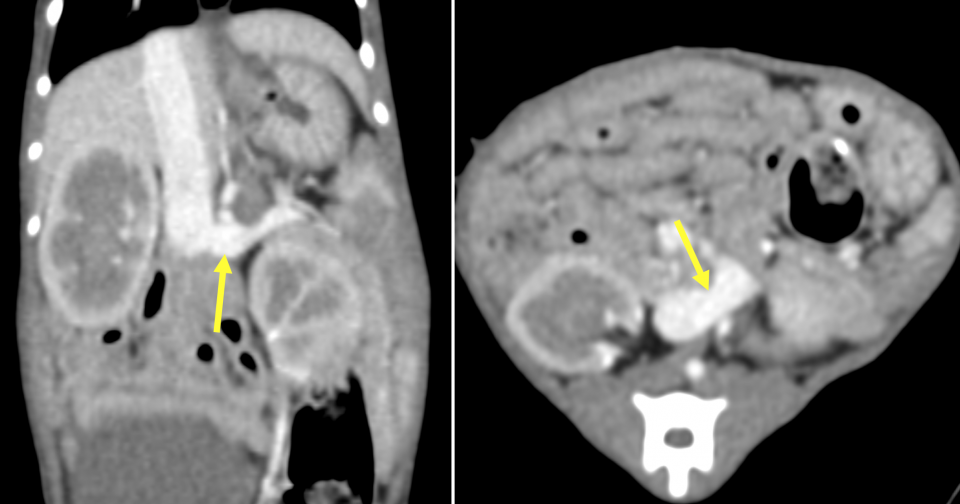

血液検査、尿検査、X線検査、腹部超音波検査などから門脈体循環シャントが疑われ、アンモニア負荷試験や総胆汁酸検査などの門脈体循環シャントで異常が見られやすい特殊検査でも異常が認められました。